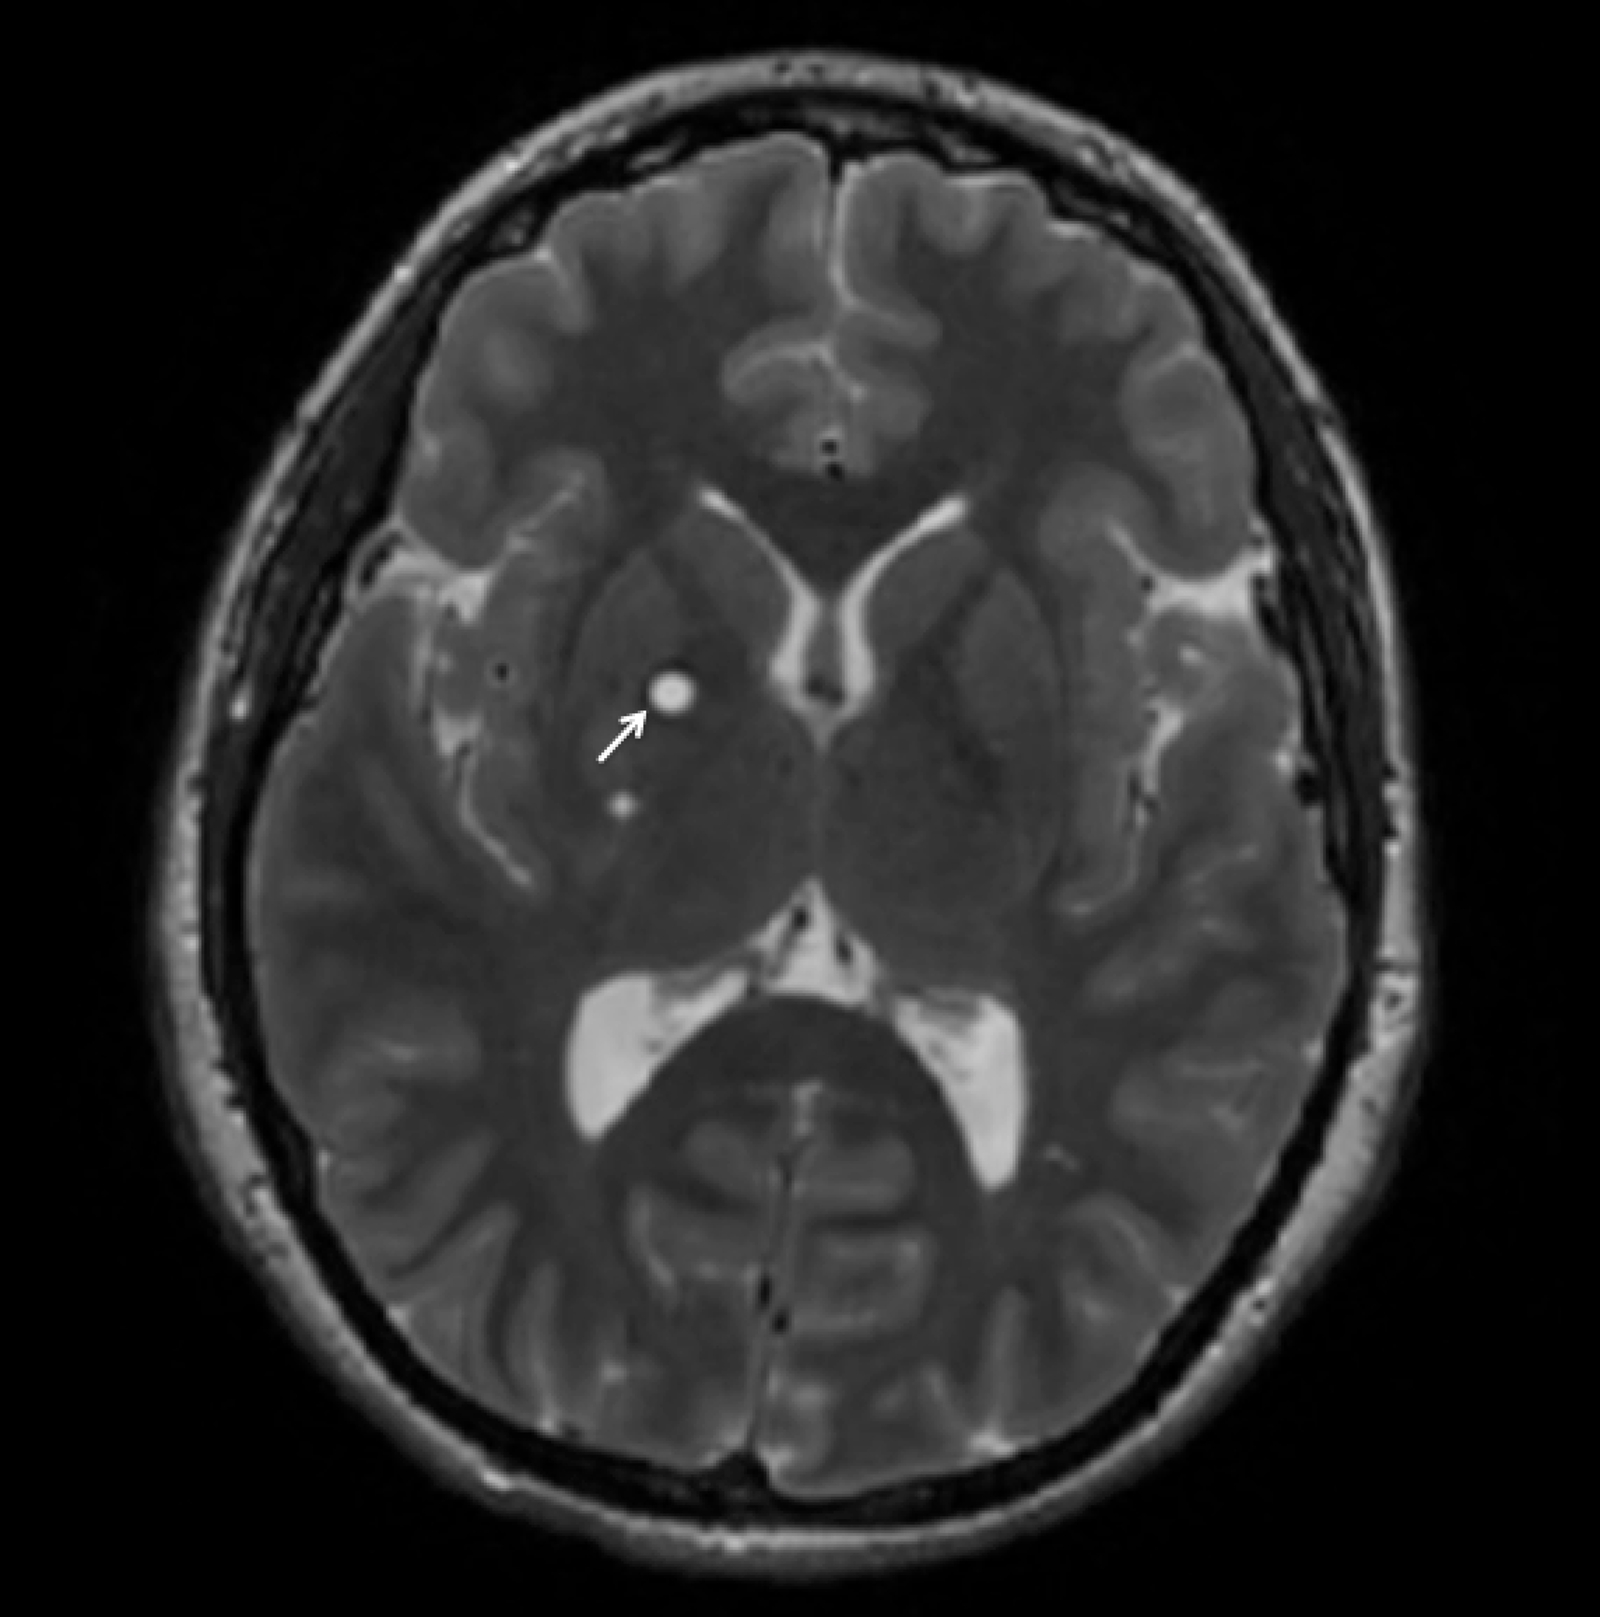

Ogniska Hiperintensywne W Obrazach T2 I Flair O Charakterze Naczyniopochodnym Subcortical FLAIR/T2 hyperintense lesions in the right upper frontal

Ogniska Hiperintensywne W Obrazach T2 I Flair O Charakterze Naczyniopochodnym | T2 weighted FLAIR image showing a 5 mm hyper intensity lesion in the